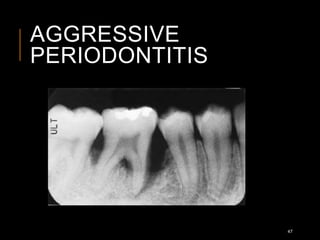

AGGRESSIVE

PERIODONTITIS